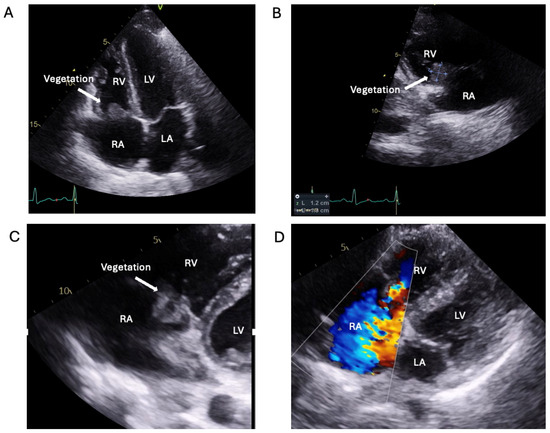

2.2. Logistical Management Challenges in a Non-Compliant High-Risk Young PWID with Relapsing Right-Sided IE